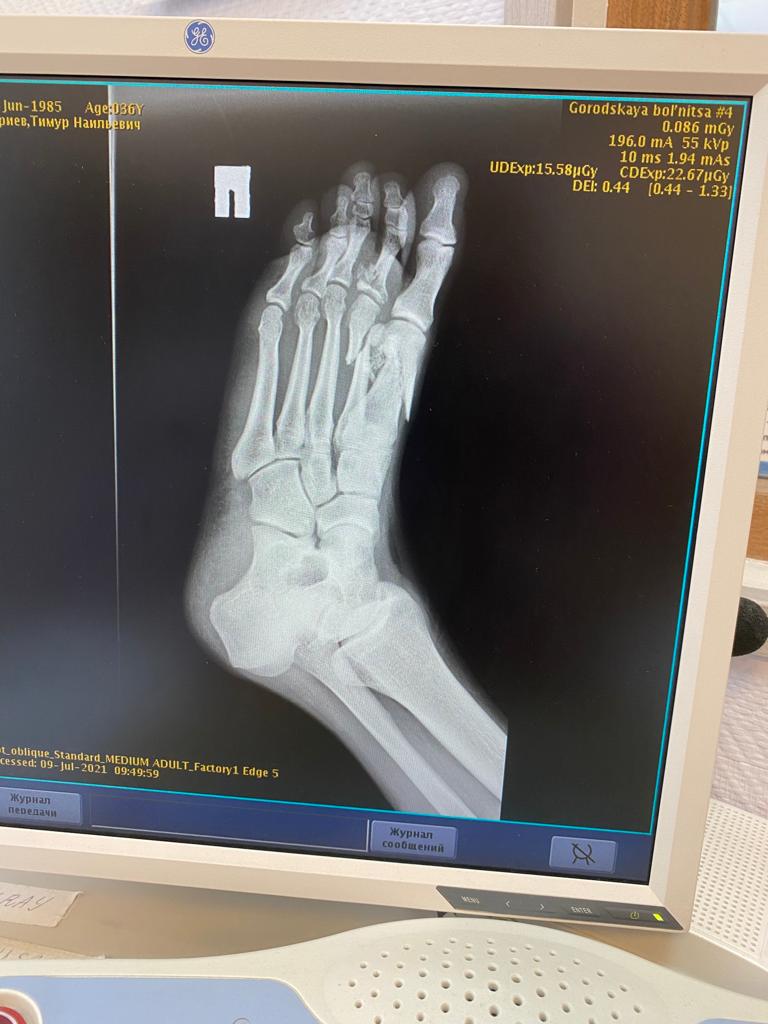

— Через полгода мне предстоит очередная операция на правую ступню. И в ближайшей перспективе протез колена левой ноги. У Александра (второй пострадавший - прим. ред.) не срослись кости на левой ноге, она у него не шевелится. 9 ноября он ложиться на операцию, будут ставить пластины, - поясняет Тимур.